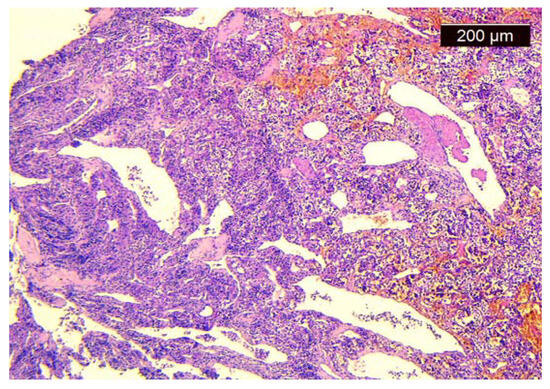

The left superior thyroid artery was exposed, divided, and ligated (Figure 4). The decision was to first try the excision through a transoral endoscopic approach with radiofrequency instruments. We performed a suspension laryngoscopy. With a radiofrequency fine needle, we attempted the resection of the tumor starting from its origin at the pyriform sinus, and we tried to protect the larynx as much as we could. Unfortunately, the bleeding was impossible to control, even after the ligation of the external carotid artery, so an external approach was chosen.

Figure 4.

Sectioning and ligation of the left superior thyroid artery (white arrow) and the external carotid artery (pointed to by the star).